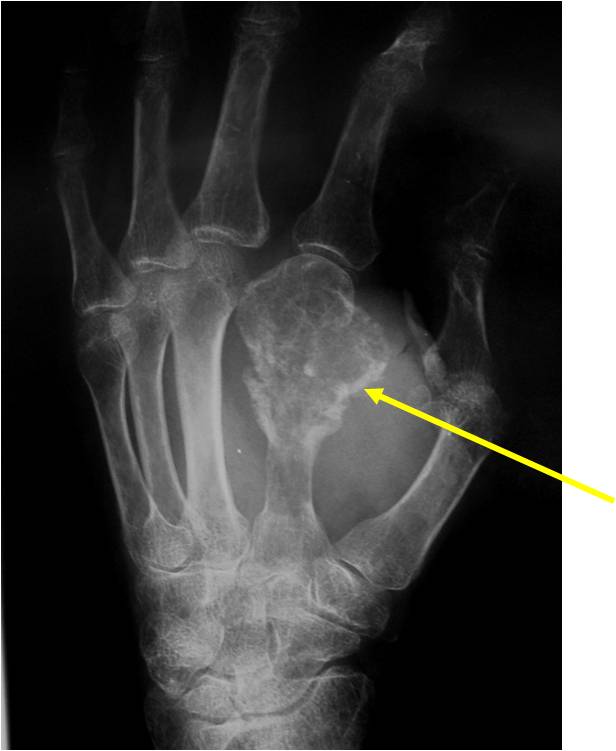

- 50% involve hands and feet (mostly phalanges)

- Cortex may be scalloped and thinned in the phalanges

- Geographic lytic lesion

- Expansile remodeling with thinned cortex

- Chondroid matrix with calcifications in majority of tumors

- Digits: Impending or actual pathological fracture

- Intralesional curettage and bone graft or cement